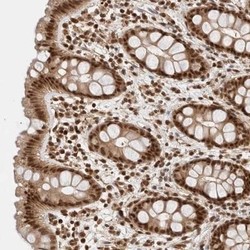

- Main image

- Experimental details

- Immunohistochemistry-Paraffin: KIAA1107 Antibody [NBP1-87546] - Staining of human rectum shows strong nuclear positivity in glandular cells.